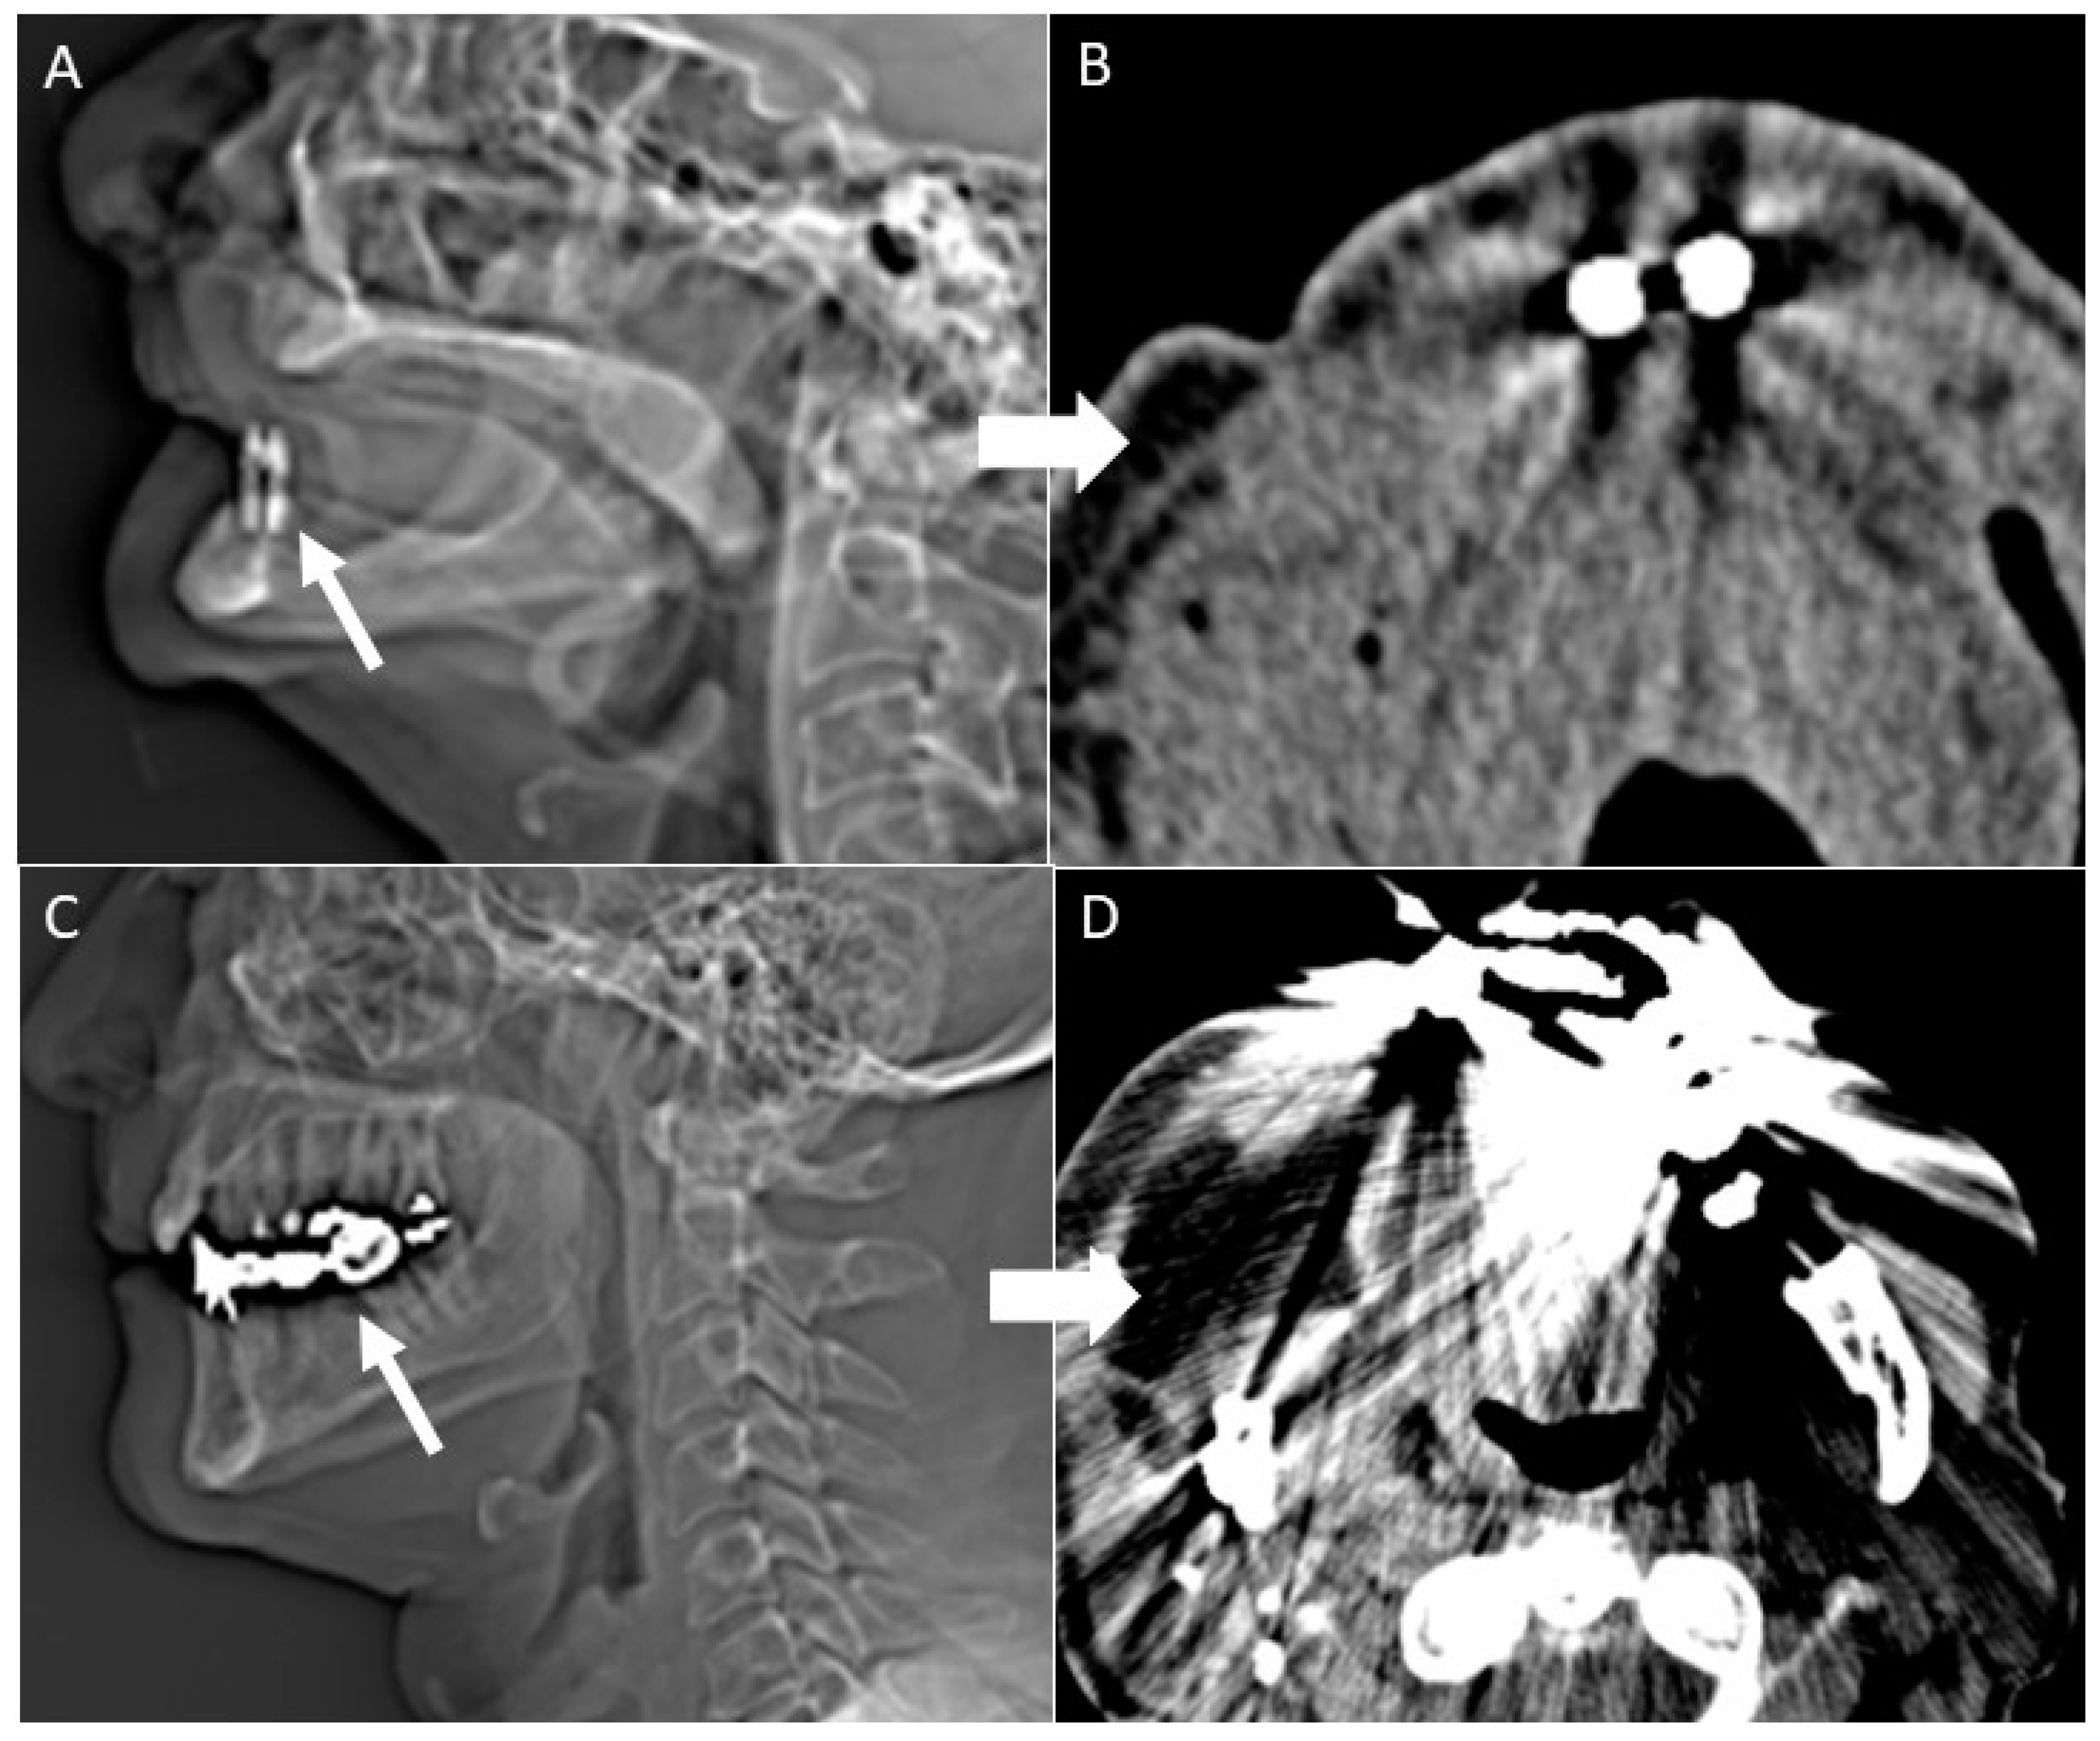

- Gantry tilt scanning. Patients have to be positioned with tooth occlusal surfaces perpendicular to the table; the gantry tilt angle used is ≥20 degrees. In the post-processing phase the oblique images obtained are reconstructed to transverse images with information on the table position [53];

- Open mouth dynamic manoeuvre. See the above-mentioned paragraph and Figure 14);